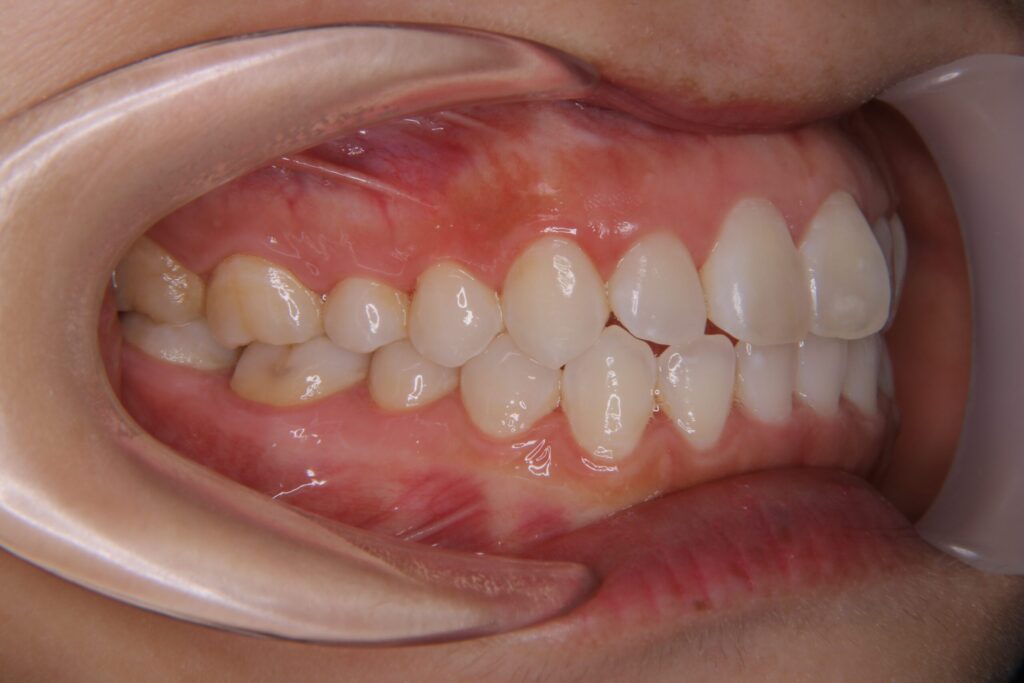

| 患者 | 28歳男性 |

|---|---|

| 主訴 | 歯ならびのガタガタ |

| 診断名 | UR7/LR7クロスバイトと上下叢生を伴うAngleⅠ級sk.1不正咬合 |

| 治療内容 | マウスピース型矯正装置(インビザライン)、部分的に上顎前歯部にワイヤー併用 |

| 抜歯の有無 | 非抜歯 |

| 治療期間 | 2年 |

| 費用(税込) | 594,000円 |

| リスクと副作用 | 痛み等、歯根吸収/歯肉退縮、後戻り、むし歯・歯肉炎の可能性。 |

【医師コメント】

上下のガタつきで来院された患者さんです。

精密検査の結果、UR7/LR7のクロスバイト(交叉咬合)と上下の叢生を伴う AngleⅠ級(sk.1)不正咬合 と診断しました。奥歯の前後関係はⅠ級で大きなズレは強くない一方、奥歯の噛み合わせのズレとスペース不足が原因でした。

治療はインビザラインを主体に非抜歯で計画し、歯列全体のバランスとかみ合わせの安定を意識しながら段階的に改善を進めました。

終盤、UL2のローテーションがわずかに残ったため、仕上げの精度を高める目的で上顎前歯部に部分的にワイヤーを併用しています。

治療は計画に沿って進行し、2年で歯列の配列とかみ合わせの改善を図ることができました。